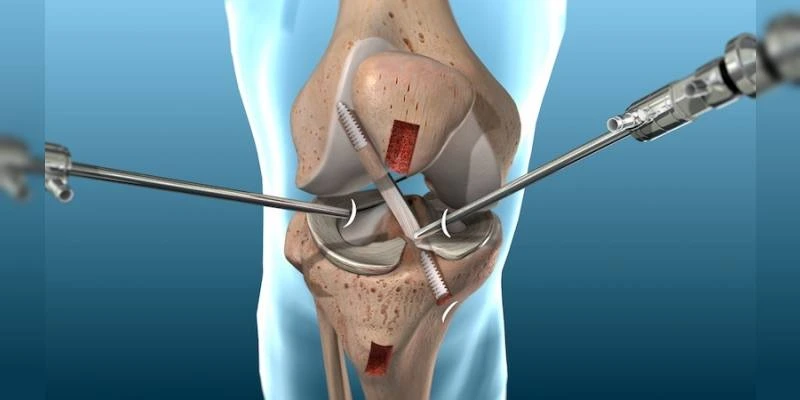

Knee arthroscopic surgery is a minimally invasive procedure used to diagnose, treat, and repair various knee joint conditions. By using small incisions and a tiny camera (arthroscope), surgeons can visualize the inside of the knee joint and perform precise repairs with minimal disruption to surrounding tissues. This advanced technique offers faster recovery, less postoperative pain, and a quicker return to daily activities compared to traditional open surgery.

Knee arthroscopy is a surgical procedure that involves inserting a small camera (arthroscope) through a small incision into the knee joint. The arthroscope allows the surgeon to see the inside of the joint on a monitor, helping to diagnose conditions and guide surgical interventions. The surgeon may also insert small surgical instruments through other small incisions to treat the condition, such as removing damaged tissue, repairing cartilage, or performing ligament reconstructions.

Ligament Injuries: Knee arthroscopy can be used to treat ligament tears, such as anterior cruciate ligament (ACL) or posterior cruciate ligament (PCL) injuries. Surgeons can repair or reconstruct these ligaments using arthroscopic techniques, improving knee stability.

Cartilage Damage: For patients with cartilage damage or chondral lesions, knee arthroscopy can be used to smooth rough areas, remove damaged tissue, or stimulate cartilage regeneration to improve joint health and function.